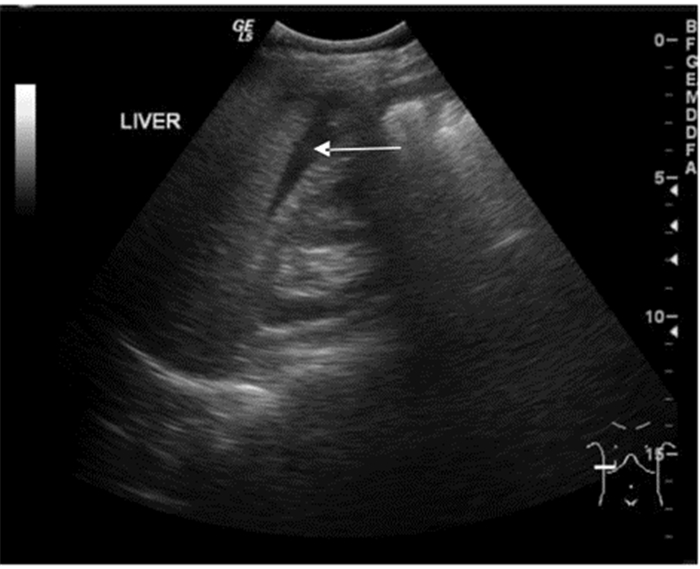

3.1.3 创伤的超声诊断的步骤及流程(1)创伤的超声诊断步骤:创伤患者床旁超声检查至少5个部位:①右上腹,也叫肝周切面、莫里森窝切面或右上1/4切面。如出现无回声区提示腹腔内出血(图 22-23)。②左上腹脾肾间隙,如出现无回声区亦提示腹腔内出血(图 24-25);③耻骨上/盆腔切面,如显示膀胱后或子宫后无回声区,提示盆腔出血可能(图 26-27);④剑突下切面,常用于探查心包有无无回声区(图 28),具体心包积液征象见2.1.2 常见异常超声心动声像图。⑤肺部超声,主要用于探查有无血气胸、肋骨骨折,具体征象见2.2肺超声。

| 图 22 肝肾隐窝部位及正常超声影像 |